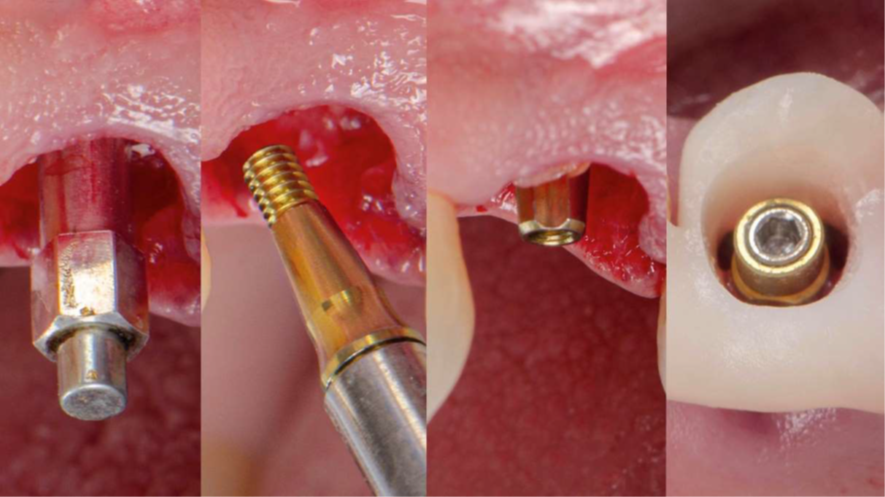

One Step, One Abutment — aplicação prática com pilar Ideale

No mesmo ato cirúrgico instalou-se o pilar Ideale definitivo, torqueado e mantido em posiçãoaté a instalação da coroa, sem remoções intermediárias. Essa conduta segue a filosofia One Step, One Abutment, que preconiza a fixação de um único pilar desde o momento cirúrgico, evitando trocas sucessivas. Cada desconexão de componente rompe o epitélio aderido, expõe o sulco peri-implantar à contaminação bacteriana e pode induzir microperdas ósseas cumulativas. Manter o mesmo pilar durante todo o tratamento permite que o tecido mole forme uma interface estável econtínua — mucointegração — estabelecendo um selo biológico protetor ao redor do implante.

A anodização dourada do pilar Ideale favorece essa mucointegração ao aumentar molhabilidade e estimular adesão de fibroblastos, gerando um contorno gengival mais natural e livre de sombreamento acinzentado — um detalhe discreto no microscópio, mas extremamente relevante no sorriso do paciente.

Confirmada a estabilidade primária por meio de ISQ acima de 70, prosseguiu-se com a instalação do provisório previamente confeccionado em impressão 3D. O modelo incluía aletas de captura para apoio nos dentes 23 e 25, garantindo estabilização inicial. Sobre o pilar Ideale, posicionou-se coifa metálica provisória, e então realizou-se a captura com resina flow, unindo o provisório impresso ao componente. Após fotopolimerização completa, a peça foi removida integralmente, permitindo acabamento extrabucal com precisão.

Nesse momento, as aletas foram removidas e o contorno foi refinado estrategicamente, respeitando zonas críticas e subcríticas do perfil de emergência, garantindo um provisório com selamento adequado do alvéolo enxertado, suporte papilar e manutenção do arquétipo gengival. O provisório finalizado foi reposicionado e colocado em função imediata. A partir daí, entra em cena a mecanotransdução: microcargas funcionais controladas atuam como estímulos biomecânicos capazes de converter forças mastigatórias em respostas celulares osteogênicas, incentivando deposição óssea, contato osso-implante e maturação do tecido peri-implantar. Em Implantodontia contemporânea, provisório não é apenas estética — é ferramenta biológica ativa que direciona cicatrização, protege o enxerto e constrói o perfil gengival definitivo.